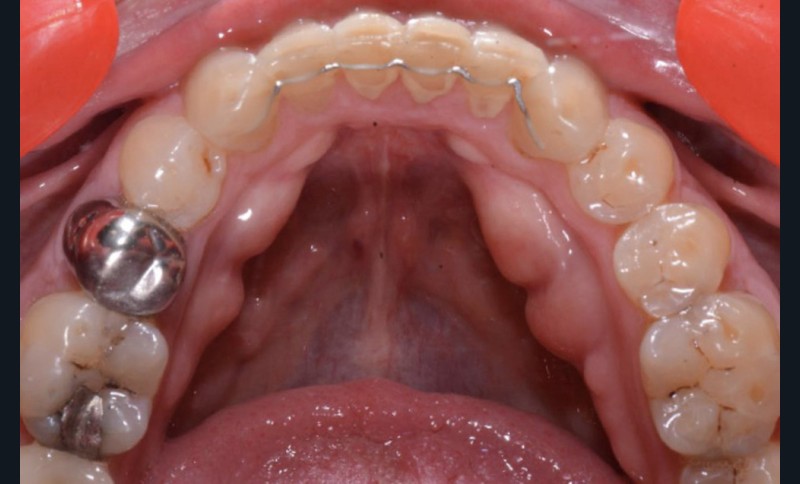

Plan de traitement

(fig. 4 à 10)

Le plan de traitement établi conjointement avec son chirurgien-dentiste traitant consiste à réaliser un alignement dentaire mandibulaire et à réaliser des extractions de 16 et 15 pour un remplacement par prothèse implanto-portée.

La durée orthodontique prévue est de neuf mois, avec comme contrainte principale l’absence de possibilités de modification des formes d’arcades.

Le gain de place se fera par des réductions interproximales sur la zone incisivo-canine mandibulaire.

Il est décidé de ne pas redresser la 43 complètement afin de ne pas entraîner d’interférences occlusales.

Un accompagnement par des meulages occlusaux est réalisé.